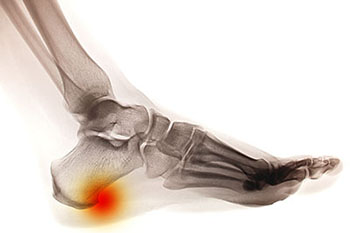

A heel spur takes the form of a bony-like growth. This is due to a calcium deposit that extends between the heel bone and foot arch. They can grow up to half an inch in length; however, they may not be outwardly visible. Because heel spurs tend to grow, increasing the overall discomfort felt, it’s important that you seek professional help as soon as pain is experienced for early detection.